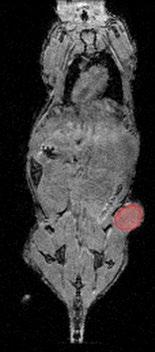

Project Title: Optimizing inference speed of 3D U-Net–based organ segmentation for automated dosimetry in molecular imaging

Molecular imaging methods such as positron emission tomography (PET) and single-photon emission computed tomography (SPECT) are used to track radioligand distribution between healthy organs and diseased tissue. However, manual segmentation of images is labor-intensive and error-prone, which is why we have developed a pipeline for automated quantification of these scans. A key component of this pipeline is a semantic segmentation model based on the nnU-Net framework2, which reduces annotation time from approximately 45 minutes to just 5 minutes per scan while achieving human-level accuracy.

The project aims to further optimize this model for inference speed by exploring improvements in network architecture3 as well as pre- and post-processing strategies. The student(s) will be responsible for implementing and benchmarking optimization techniques, conducting controlled experiments, and analyzing the trade-offs between computational efficiency, segmentation accuracy, and robustness. For this project, students will have access to a large, internally developed dataset of native mouse and rat computed tomography (CT) scans with corresponding organ annotations. This unpublished dataset ensures that the project can focus on methodological and computational aspects, while also providing opportunities for novel research contributions.

PREVIOUS STUDY ON THE TRADE-OFFS IN SEGMENTATION PERFORMANCE AND SEGMENTATION MODEL ARCHITECTURE ON AN INTERNAL DATASET OF RAT AND MOUSE NATIVE CT SCANS